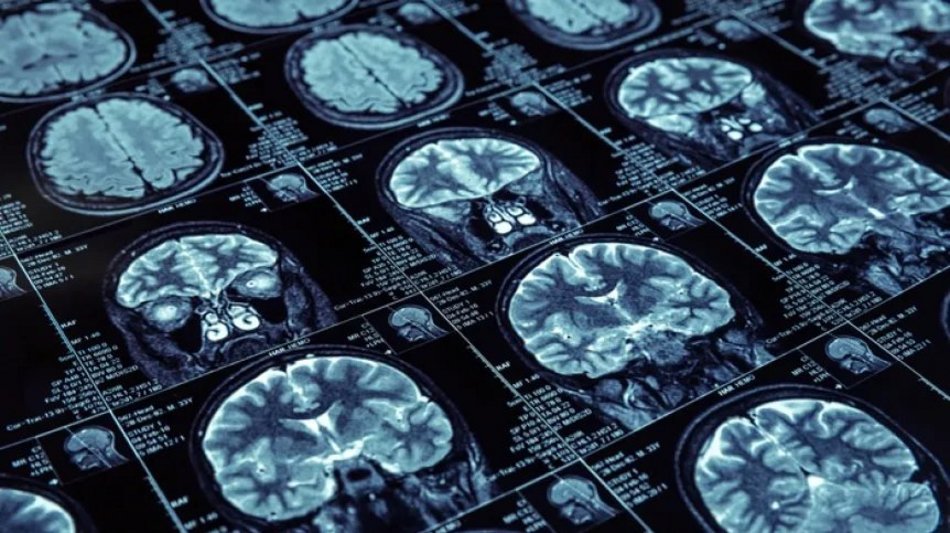

wróć do artykułu Zmieniaj zdjęcia za pomocą strzałek na klawiaturze 2 / 3 Przełom w leczeniu raka w Szpitalu Kopernika w Łodzi! Lekarze usunęli glejaka innowacyjną metodą Przełom w leczeniu raka w Szpitalu Kopernika w Łodzi! Lekarze usunęli glejaka innowacyjną metodą ZOBACZ TAKŻE Program „Moje Zdrowie” w Łodzi. Sprawdź, jak skorzystać z darmowych badań w MCM Polesie Pudełka, które ratują życie! Gdzie w Łodzi zgłosić się po ten gadżet? [SZCZEGÓŁY] Cud w Szpitalu Kopernika w Łodzi! Uratowano pacjenta, którego serce nie biło przez 11 godzin